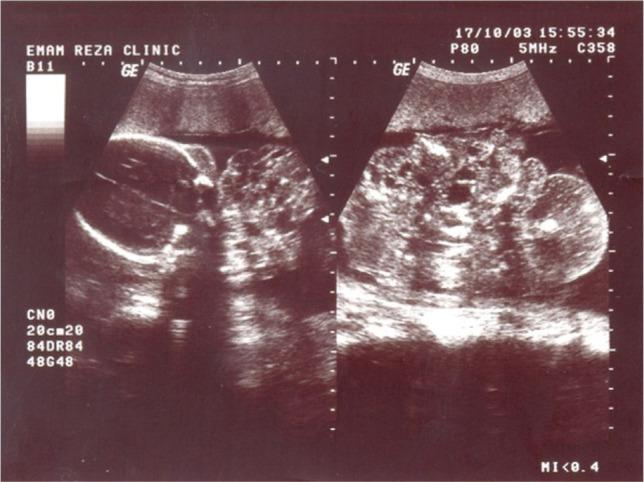

Epignathus is a rare congenital orofacial teratoma. Teratomas are tumors that originate from all three germs cell layers. Tumor size is an important prognostic factor, and we describe the case of massive epignathus identified by sonography at 25 weeks. Our case was a 35-year-old pregnant woman that was subjected to a routine ultrasound at 25 weeks of gestation, and epignathus was diagnosed. Labor pain started in the 28th week of the pregnancy, so the dead fetus was aborted, and curettage was conducted. A pathologic sample was sent to the laboratory, and benign teratoma was diagnosed. Because fetal epignathus has a wide range of outcomes, early prenatal diagnosis is essential for optimal management.

上颌寄生胎是一种罕见的先天性口面部畸胎瘤。畸胎瘤是起源于所有三个胚层的肿瘤。肿瘤大小是一个重要的预后因素,我们描述了一例在孕25周时通过超声检查发现的巨大上颌寄生胎病例。我们的病例是一名35岁的孕妇,在妊娠25周时接受常规超声检查,诊断为上颌寄生胎。妊娠第28周开始出现宫缩痛,于是引产并进行了刮宫术。将病理样本送检,诊断为良性畸胎瘤。由于胎儿上颌寄生胎的预后差异很大,早期产前诊断对于最佳治疗至关重要。